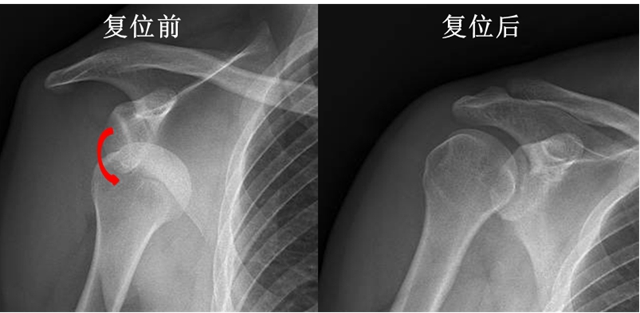

由于脱位时引起的肩关节囊韧带的撕脱伤,由于这种撕脱伤保守治疗很难使其达到愈合,因而造成脱位反复发作。

对于已经形成习惯性肩关节脱位的患者,保守治疗的复发概率较高,所以目前以手术治疗为主。

手术治疗较常用的是关节镜下的关节囊-盂唇重建术。

该手术只需要打几个5毫米的小孔,再将3-4个直径仅有2.8毫米的小螺钉放入,一个小时就搞定了。